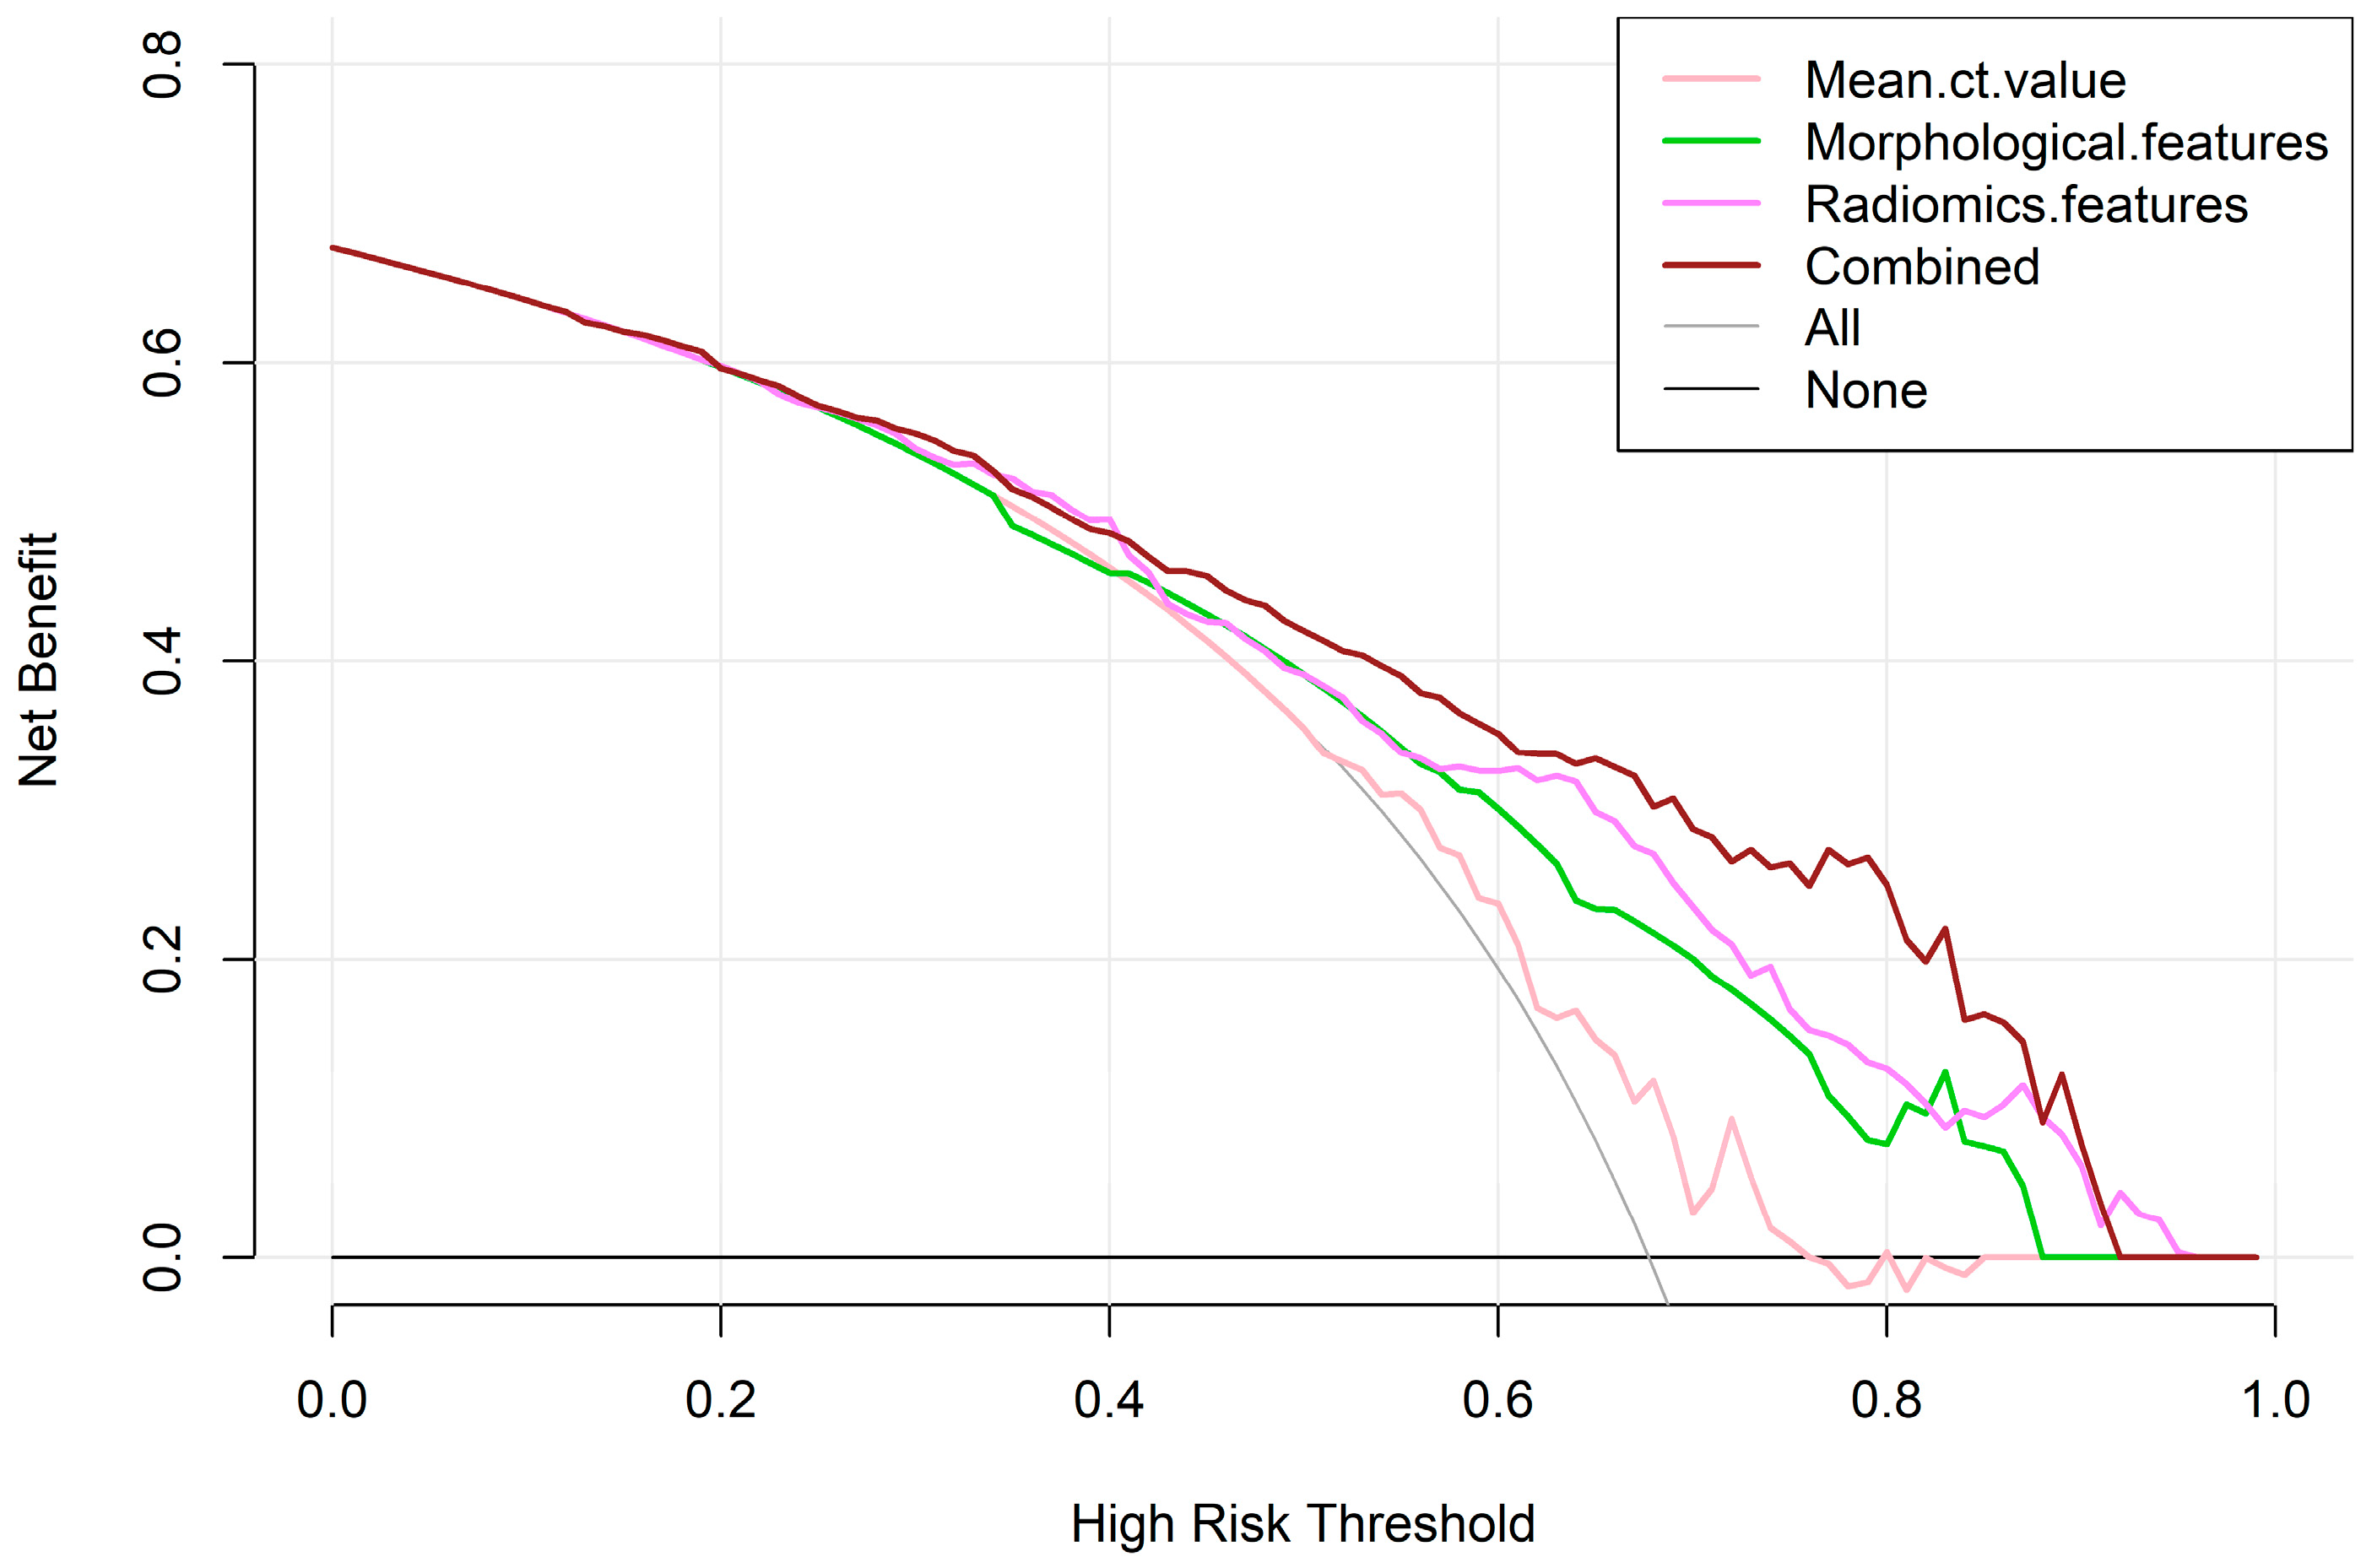

3.3. Construction and Diagnostic Performance of Predictive Models